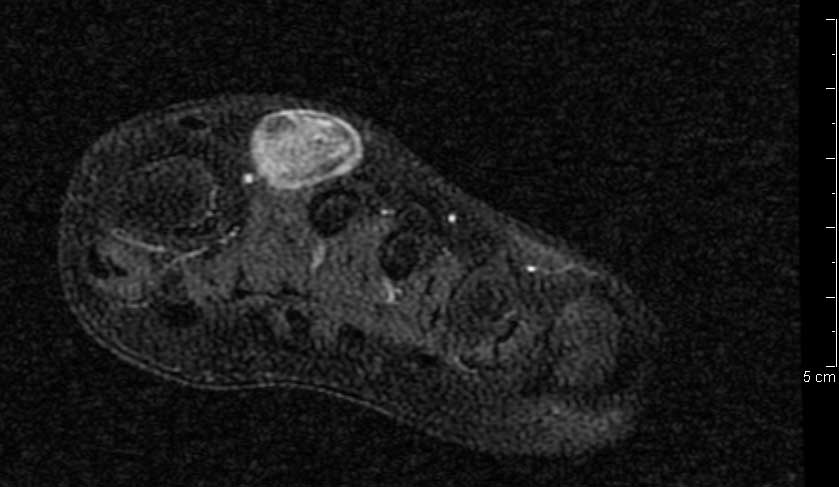

Figura 3. Presenza di flusso in parete. � stata effettuata una RMN con contrasto con acquisizioni multiplanari T1 e T2 pesate anche con tecnica di soppressione del grasso, con il rilievo di una formazione ovalare di 16 x 12 x 20 mm a margini regolari con iperintensit� di segnale centrale nelle pesate T1 e T2 dipendenti, e componente periferica sottile che subisce enhancement contrastografico, in apparente continuit� anatomica con struttura vascolare del fascio vascolo-nervoso dorsale, ascrivibile, in primis, a formazione vascolare o patologia vascolare dilatativa trombizzata (Figure 4, 5 e 6). ![]() |

Figura 5.Scansione sagittale T1 pesata SE. |

Figura 6.Ricostruzione MIP. In questa breve sequenza di immagini si pu� notare il passaggio dal lume vascolare normale alla porzione ectasica e quindi di nuovo al calibro regolare (Figura 7). ![]() ![]() ![]() ![]() ![]() ![]() |

Figura 7. Serie di tomogrammi assiali STIR. L�intervento � stato condotto con l�induzione di una breve anestesia generale e l�escissione completa della formazione (Figura 8, 9 e 10).